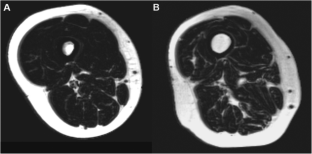

Muscle mass is particularly relevant to follow during aging, owing to its link with physical performance and autonomy. The objectives of this work were to assess muscle volume (MV) and intramuscular fat (IMF) for all the muscles of the thigh in a large population of young and elderly healthy individuals using magnetic resonance imaging (MRI) to test the effect of gender and age on MV and IMF and to determine the best representative slice for the estimation of MV and IMF. The study enrolled 105 healthy young (range 20–30 years) and older (range 70–80 years) subjects. MRI scans were acquired along the femur length using a three-dimension three-point Dixon proton density-weighted gradient echo sequence. MV and IMF were estimated from all the slices. The effects of age and gender on MV and IMF were assessed. Predictive equations for MV and IMF were established using a single slice at various femur levels for each muscle in order to reduce the analysis process. MV was decreased with aging in both genders, particularly in the quadriceps femoris. IMF was largely increased with aging in men and, to a lesser extent, in women. Percentages of MV decrease and IMF increase with aging varied according to the muscle. Predictive equations to predict MV and IMF from single slices are provided and were validated. This study is the first one to provide muscle volume and intramuscular fat infiltration in all the muscles of the thigh in a large population of young and elderly healthy subjects.

Fig. 1

Fig. 2

Fig. 3